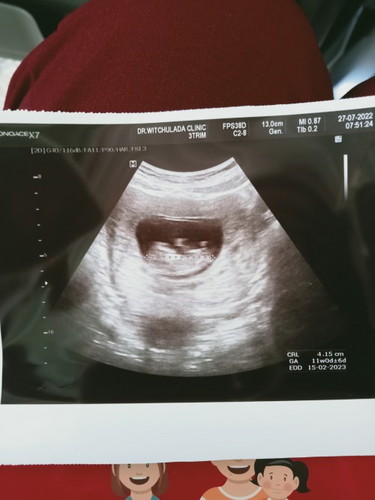

ในสมุดสีชมพูคุณหมอเขียน10w3D แต่ในใบอัตราซาวด์11Wเราก็เชื่ออันไหนค่ะ รบกวนแม่ๆที่ประสบการณ์ตอบหน่อยจ้า